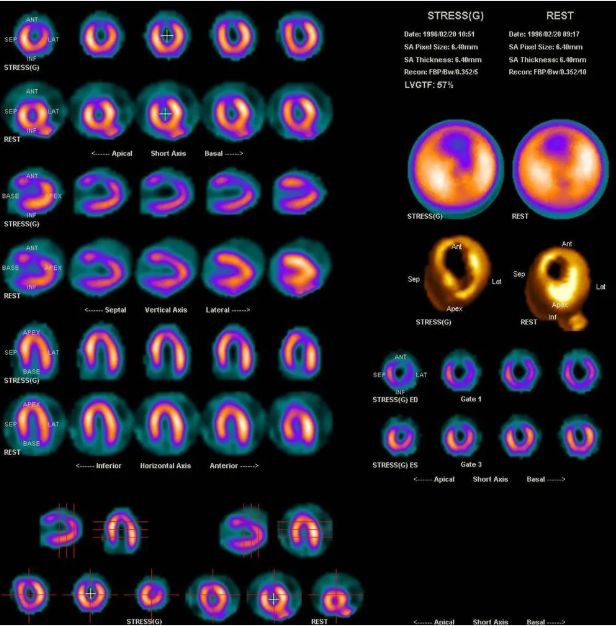

心肌灌注/代谢显像

冠心病心肌缺血的诊断、危险度的分层、疗效评价、心肌病、糖尿病心肌损害、微血管性心绞痛、心肌细胞的存活等。

▲心肌灌注显像